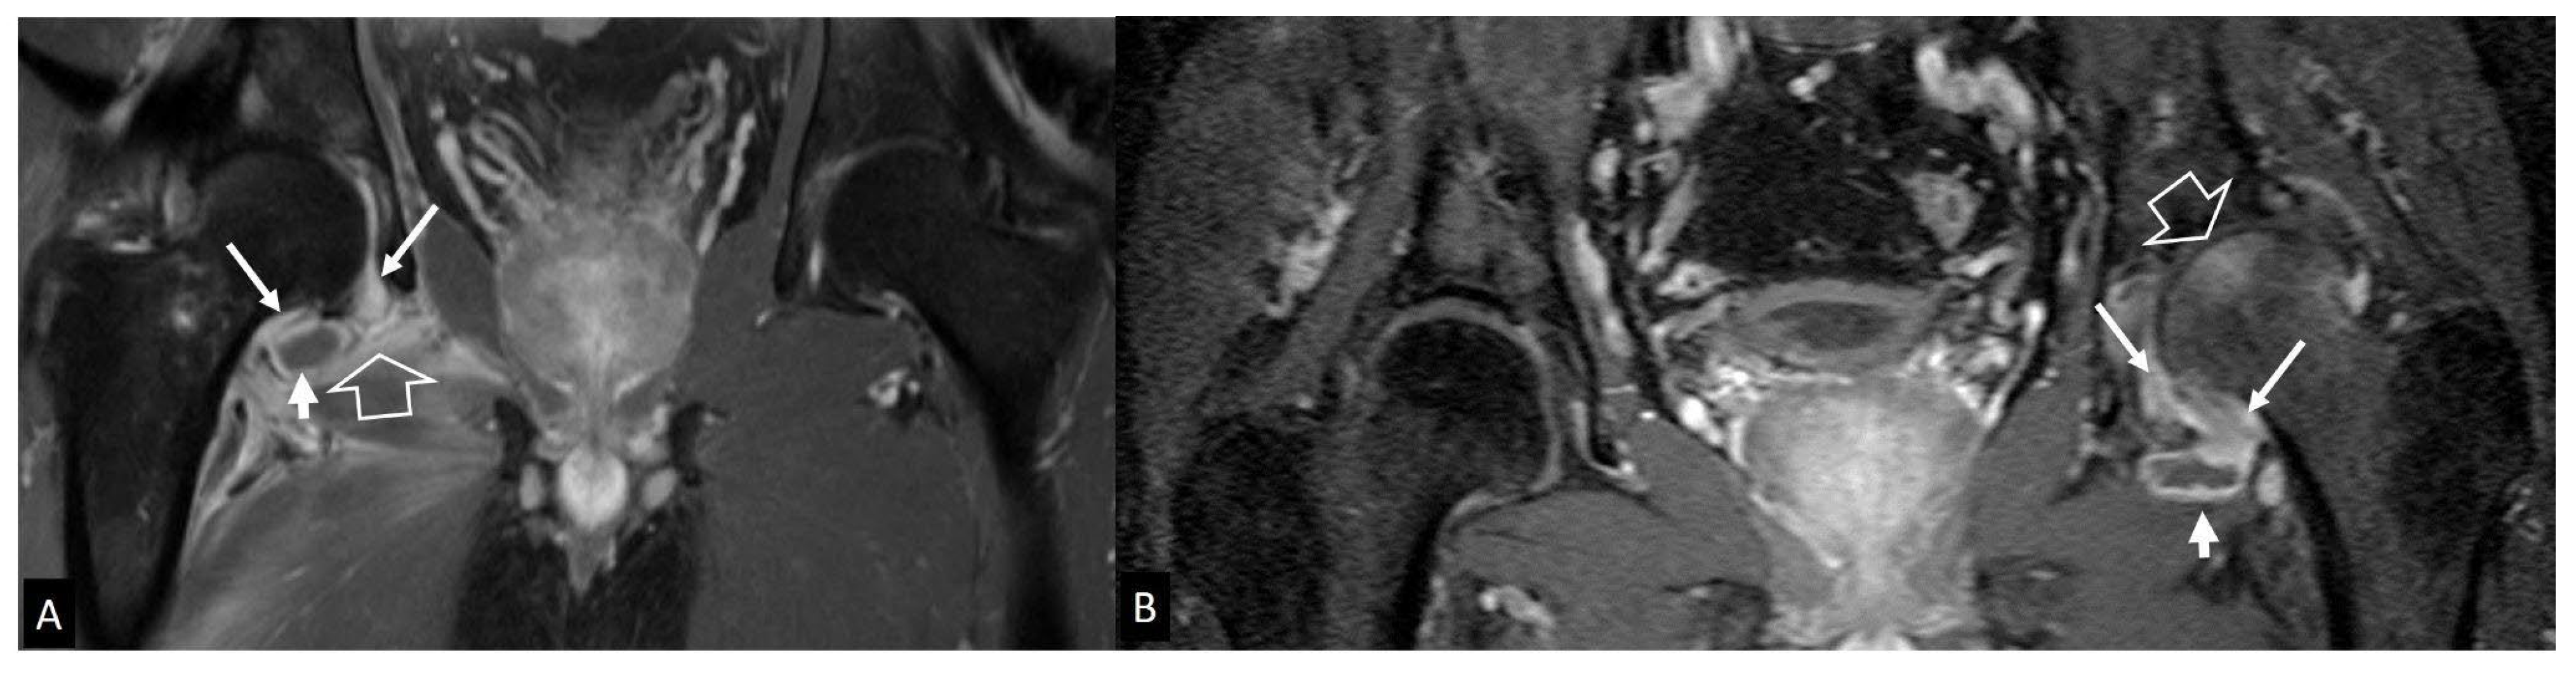

3. b.i. Inflammatory Arthritis

3. b.ii. Neuropathic Arthropathy

3. b.iii Crystal-Induced Arthropathies

3. b.iv. Rapidly Destructive Osteoarthritis of the Hip